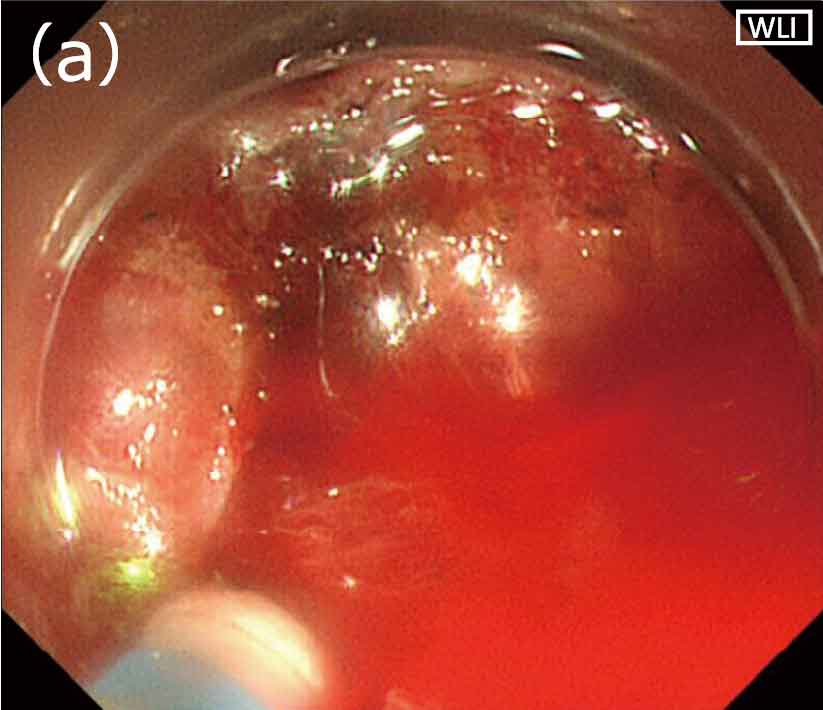

RDIモード下で微小出血であると確認した場合は、止血処置は行わずにESDを続行しています。静脈からの湧出性出血や小動脈からの出血と思われるような軽度の出血の場合(図3a)は、止血鉗子は使用せず格納したナイフ先端(DualKnifeJ)で接触凝固を行っています(図3b)。太めの動脈からの噴出性出血など、中等度から重度の出血の場合、従来の白色光観察では一瞬にして画面全体が赤くなってしまうことが多く、吸引や洗浄を行っても出血点の視認は困難でした(図4a)。しかしRDIモード下では、吸引や洗浄を行っている間に出血点が濃いアンバー色として描出されるため、容易に同定が可能です(図4b)。血液が多量に貯留した状態では、RDIモードに切り替えても、出血点の確認は困難となります。

〈図4〉中等度の出血の視野比較(a)白色光観察;(b)RDIモード